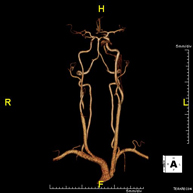

Prueba diagnóstica no invasiva que consiste en la obtención de imágenes de alta definición anatómica de las arterias carótidas y vertebrales a nivel de cuello, mediante el empleo de un campo electromagnético y ondas de radio (con un emisor y un receptor). No utiliza radiación ionizante. En la mayoría de los casos es necesario el empleo de contraste paramagnético (Gadolinio). Permite un estudio angiográfico no invasivo gracias a la inyección de Gadolinio con posterior reconstrucción en 2D y 3D, gracias a estaciones de trabajo especializadas. Indicaciones: problemas circulatorios cerebrales, síncope. - RM Espectroscopia Cerebral

Prova diagnòstica no invasiva que consisteix en l'obtenció d'imatges d'alta definició anatòmica de les artèries caròtides i vertebrals a nivell de coll mitjançant l'ús d'un camp electromagnètic i ones de ràdio (amb un emissor i un receptor). No utilitza radiació ionitzant. En la majoria dels casos és necessari l'ús de contrast paramagnètic (Gadolini). Permet un estudi angiogràfic no invasiu gràcies a la injecció de Gadolini amb posterior reconstrucció en 2D i 3D, gràcies a estacions de treball especialitzades. Indicacions: problemes circulatoris cerebrals i síncope. - Angio-RM d'Aorta Toràcica